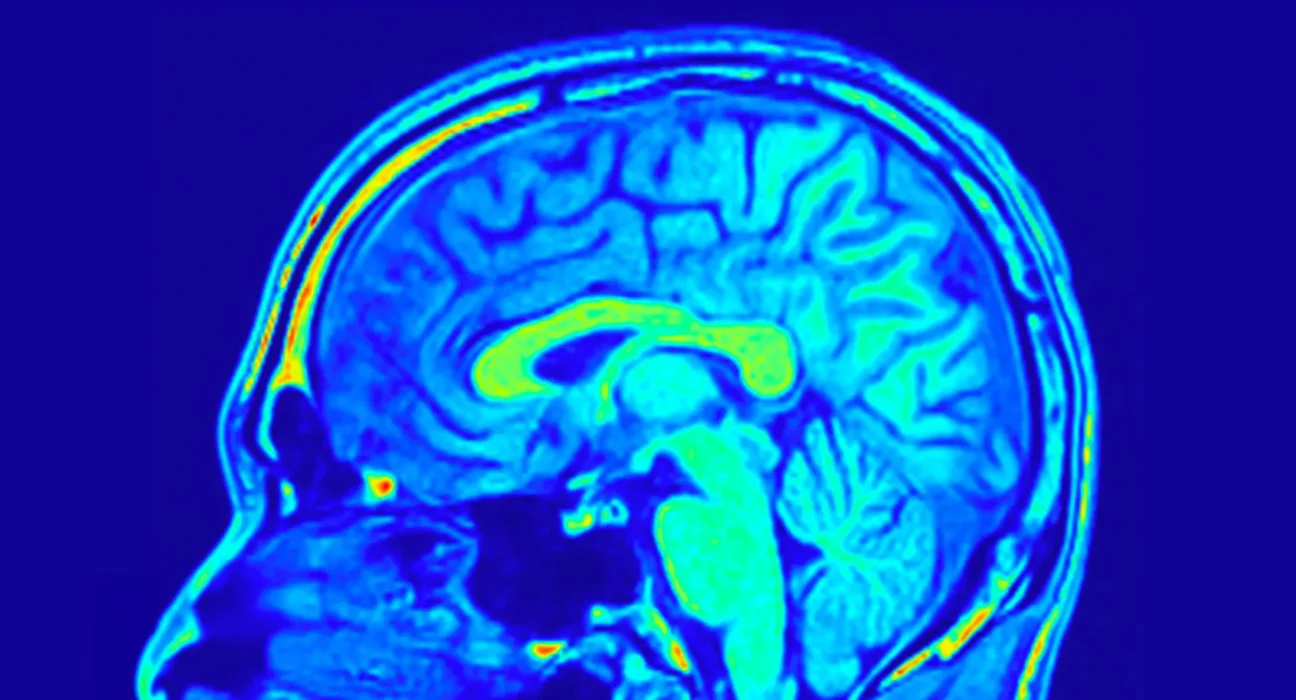

O córtex cerebral humano tem apenas alguns milímetros de espessura e é organizado em várias dobras. Este tecido geralmente se torna mais fino com a idade. “Isso é uma característica do envelhecimento. Atribui-se isso, entre outras coisas, à perda de neurônios. Como resultado, algumas habilidades deterioram-se. De qualquer forma, geralmente se assume que menos volume cerebral significa função reduzida”, explica a Prof. Esther Kühn, neurocientista do DZNE e do Instituto Hertie de Pesquisa Clínica do Cérebro. “No entanto, sabe-se pouco sobre como exatamente o córtex realmente envelhece. Isso é notável, tendo em vista que muitas das nossas atividades diárias dependem de um córtex funcional. É por isso que examinamos a situação com exames de ressonância magnética de alta resolução.”

Utilizando ressonância magnética (MRI), os pesquisadores conseguiram mapear essa área do córtex cerebral com uma precisão nunca antes vista. Para isso, eles utilizaram um scanner particularmente sensível com uma intensidade de campo magnético de sete Tesla, permitindo que eles imagerem estruturas cerebrais minúsculas, do tamanho de um grão de areia. Um total de cerca de 60 mulheres e homens com idades entre 21 e 80 anos foram examinados. “Até agora, não se considerava que o córtex somatossensorial primário consistisse em uma pilha de várias camadas extremamente finas de tecido, cada uma com sua própria arquitetura e função. Agora descobrimos que essas camadas envelhecem de maneira diferente. Embora o córtex cerebral se torne mais fino globalmente, algumas camadas permanecem estáveis ou, surpreendentemente, até se tornam mais grossas com a idade. Presumivelmente porque são particularmente solicitadas e, portanto, mantêm sua funcionalidade. Assim, vemos evidências de neuroplasticidade, ou seja, adaptabilidade, mesmo em pessoas idosas.”